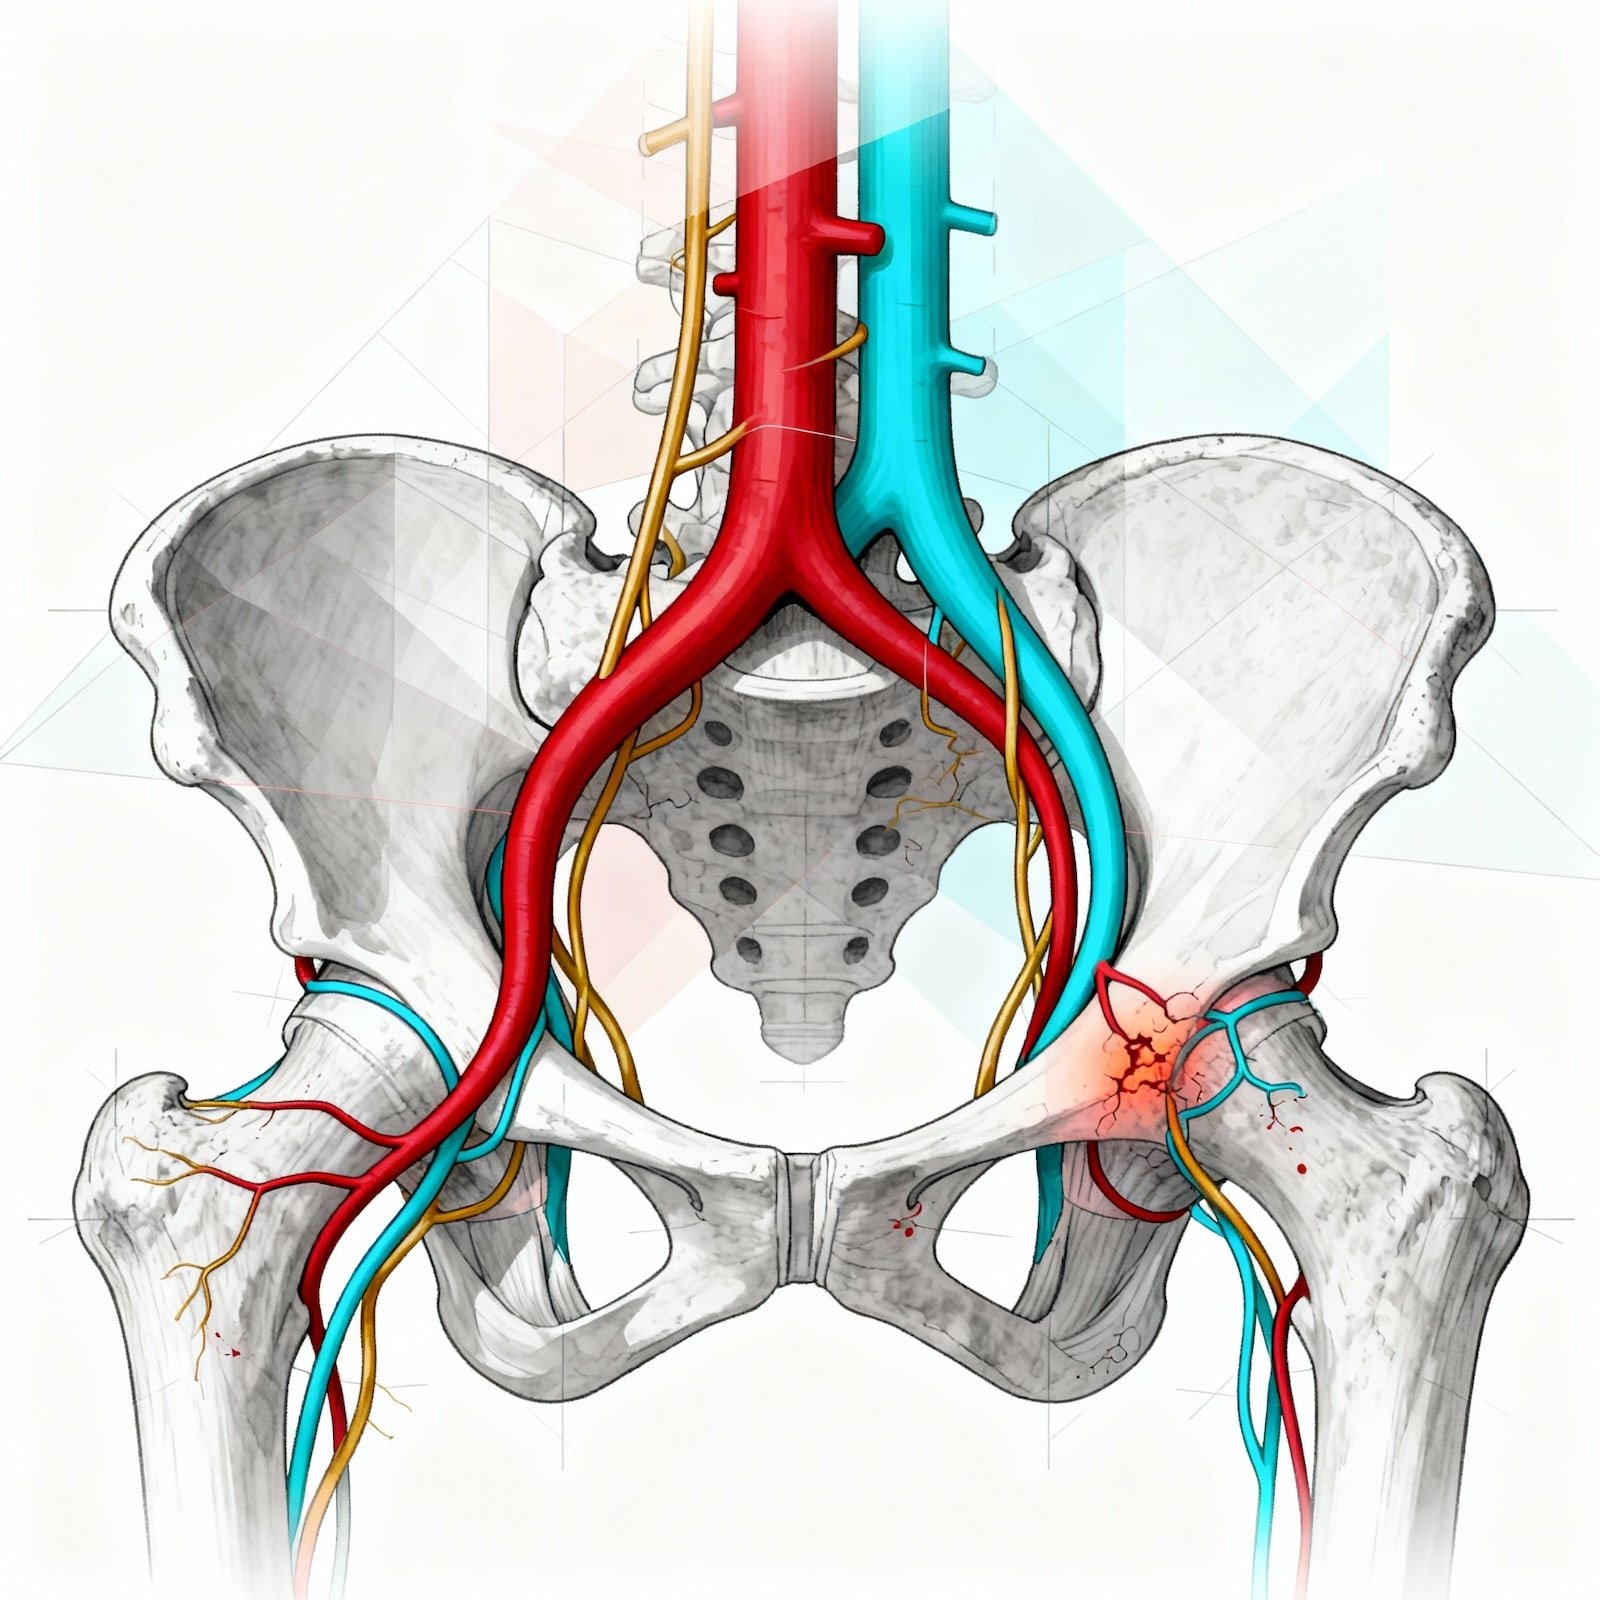

O nervo pudendo origina-se nas raízes sacrais S2, S3 e S4 da coluna vertebral. Ele percorre um trajeto tortuoso através da pelve, passando por ligamentos rígidos e túneis musculares (como o Canal de Alcock), o que o torna anatomicamente suscetível a aprisionamentos mecânicos.

O nervo pudendo conecta a coluna a áreas vitais. A dor pode ocorrer em qualquer ponto deste caminho: